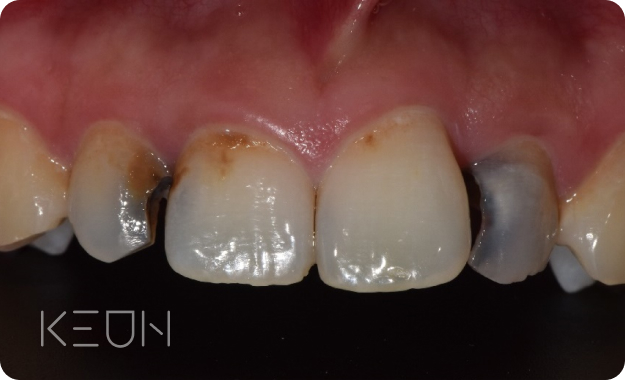

크라운

광범위한 치아의 손상 시 치아의 머리 부분을 전체적으로 씌우는 방법

- Before

로그인 후 확인 하실 수 있습니다!- After